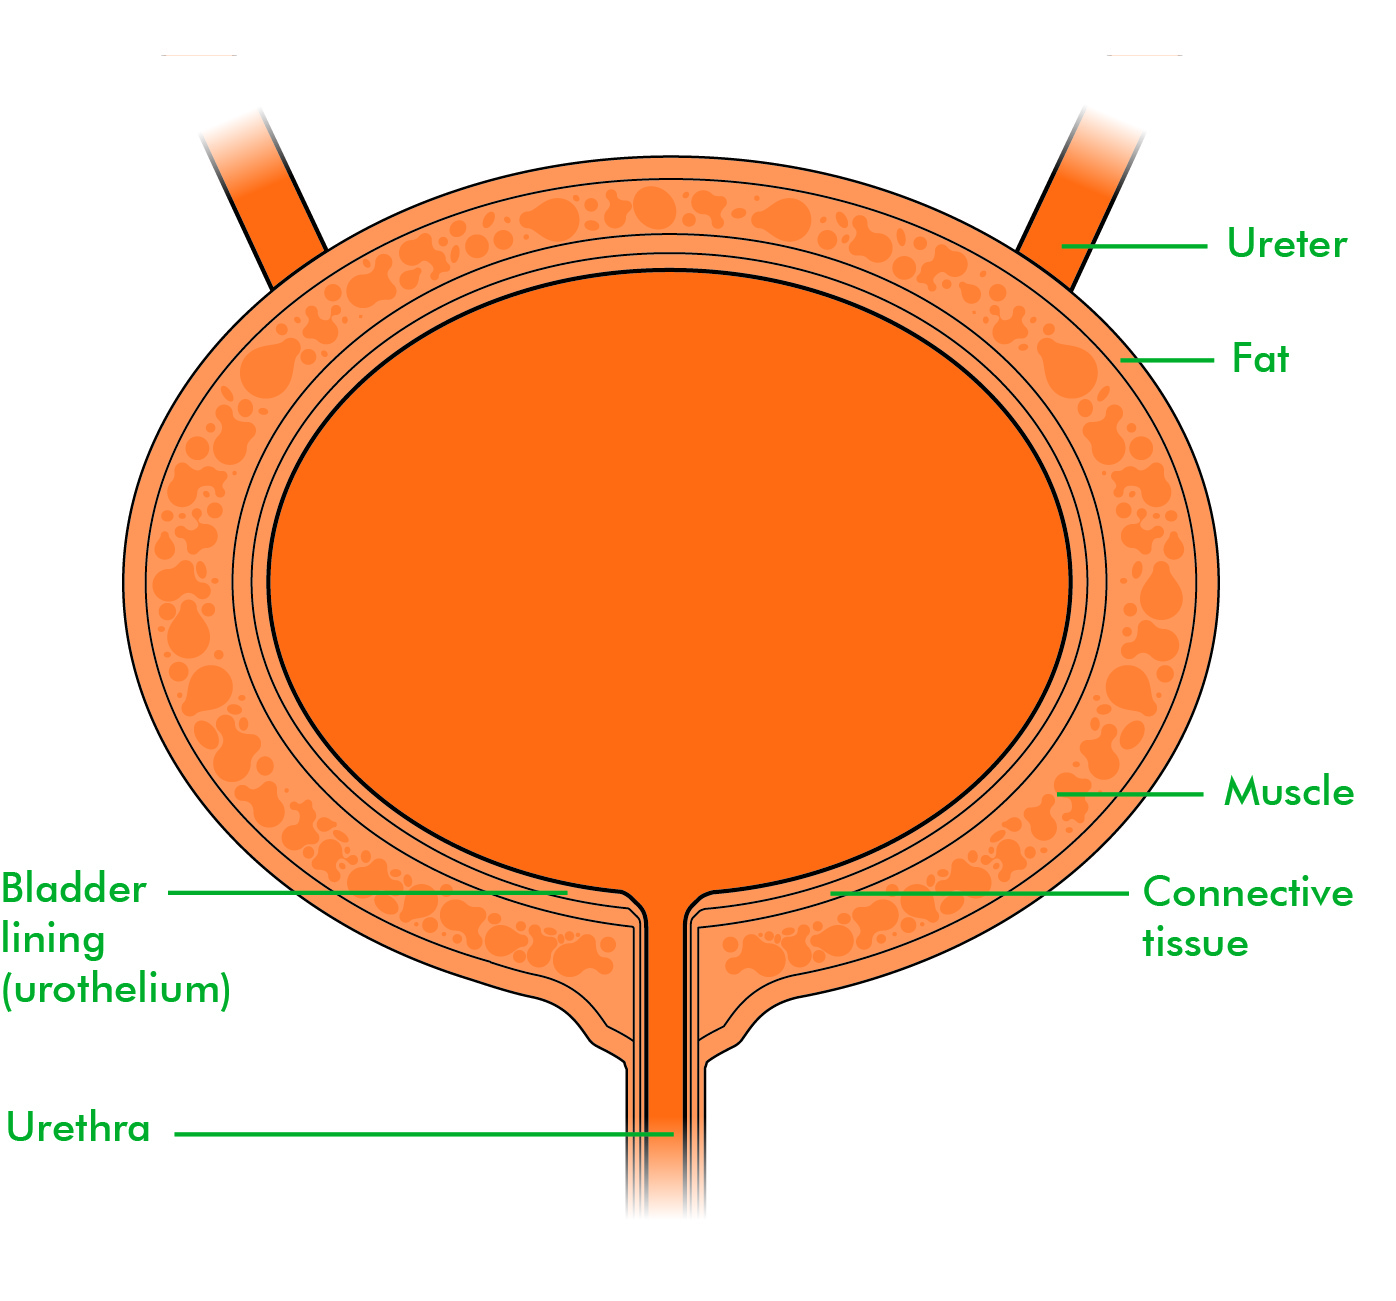

location of the bladder in the human body

Posts: location of the bladder in the human body